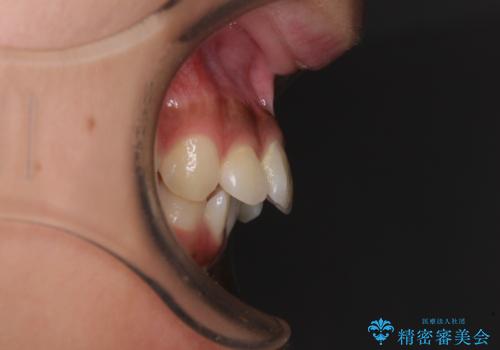

- 下唇に上顎前歯の跡がつくくらいに突出した前歯とデコボコを気にして来院された患者様です。

口元の突出感改善のため、上下左右の第一小臼歯4本を抜歯し、ワイヤー装置にて矯正治療を行うこととしました。

それほど口元の突出感が強いわけではありませんでしたが、下唇に前歯引っかかる感触が気になっていたため、抜歯矯正を行うこととしました。